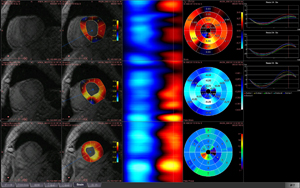

今回ITEMで初めて紹介されるziostation2の最新バージョンでは,従来から定評のある脳血流解析に加え,膵血流など体幹部の解析も可能にした「CT/MR血流解析」,「CTボリューム血流解析」,Dual Energy CT装置のデータを用いて抽出したい物質のCT値の範囲を指定しボリューム情報を分離する「D.E.デコンポジション」,神経線維の走行解析を行い,さらにMRAやCTAともフュージョン可能な「MRトラクトグラフィー」などを新たに搭載しました。より幅広い分野の検査をサポートします。 このほか,次期バージョンで搭載予定のMR心臓検査画像から右心室の機能解析を行う「MR右心機能解析」や 心壁の局所的な壁運動の異常を解析する「MRストレイン解析」なども紹介します。

| 演題・演者: | 「PhyZiodynamicsの特徴と展望」 小林 泰之 先生 / 聖マリアンナ医科大学 放射線医学画像診断部門 講師 「PhyZiodynamicsによる虚血心筋や心同期性障害の定量化の試み」 長尾 充展 先生 / 九州大学大学院 医学研究室 分子イメージング・診断学講座 准教授 |